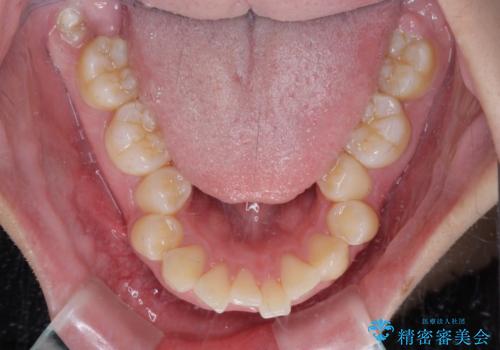

- 上顎前歯が飛び出していて唇がうまく閉じられないとのことで来院された患者様です。

くちばしのように前歯が突出していたため、口元を積極的に引っ込めるために、上下左右の小臼歯4本を抜歯することとしました。

上下正中位置を改善するため、左下はイレギュラーに第二小臼歯を抜歯しました。そのため治療期間の長期化が予想されましたが、2年半ほどで期待通りの歯列に仕上げることができました。